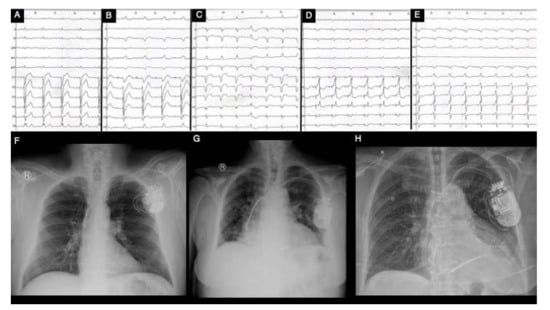

Current international guidelines recommend standard surface ECG with QRS duration measurement for establishing the indication of CRT, regardless of patients’ disease. Nevertheless, the major shortcoming in surface ECG is that it cannot accurately characterize various myocardial activation irregularities and it presents with a wide variety in defining LBBB, both leading to a significant number of patients who are CRT non-responders [9]. Additionally, the inhomogeneity in identifying and categorizing LBBB is caused by gaps in its proper definition, guidelines’ unevenness and intra- and inter-observer variability [52,53]. Hence, in a meta-analysis conducted by Cleland et al., which evaluated 3782 patients with proper recommendation for CRT, amongst QRS duration, LVEF and LBBB morphology, solely QRS interval was independently associated with all-cause mortality and hospitalization for HF [53]. Moreover, patients who exhibit NICD are also candidates for CRT, mainly based on their QRS duration; however, there is a considerable inconsistency in their response rate, especially due to the underlying myocardial illnesses [54]. More than that, in a study conducted by Kawata et al., which evaluated the impact of CRT in patients with NICD and right bundle branch block, only QRS duration of over 150 ms was associated with a positive response rate [55]. Thus, in patients with HCM, not solely the LBBB morphology should determine CRT, but rather the QRS duration should also be always taken into account. Various ECG morphologies can be found in Figure 5.

Figure 5. Clinical vignette of LBBB and post-CRT electrical patterns and post-procedural radiological anatomy in patients with hypertrophic cardiomyopathy treated with CRT (own collection of authors). (A)—typical LBBB activation; (B)—prior AAIR pacing for sinus node disease with atypical LBBB activation; (C)—atypical LBBB with apical aneurysm in midventricular hypertrophy pattern HCM; (D)—DDDR programming with LV-only pacing in optimal fusion intervals in an HCM patient with LBBB; (E)—DDD programming with biventricular pacing in an HCM patient; (F)—post-procedural radiological aspect of CRT-D device with mid-septal position of single-coil RV lead and posterolateral position of LV bipolar lead in a non-dilated hypokinetic HCM patient; (G)—post-procedural radiological aspect of a preexisting single-chamber ICD upgraded to CRT-D with a mid-septal position of dual-coil RV lead and posterolateral position of LV tetrapolar lead in a patient with end-stage dilated phenotype of HCM with severe LV dysfunction with newly developed LBBB; (H)—post-procedural radiological CRT aspect with mid-septal position of single-coil RV lead and posterolateral position tetrapolar multipoint LV lead in a patient with prior surgical septal myectomy. Abbreviations: LBBB, left bundle branch block; CRT, cardiac resynchronization therapy; HCM, hypertrophic cardiomyopathy; RV, right ventricle; LV, left ventricle.